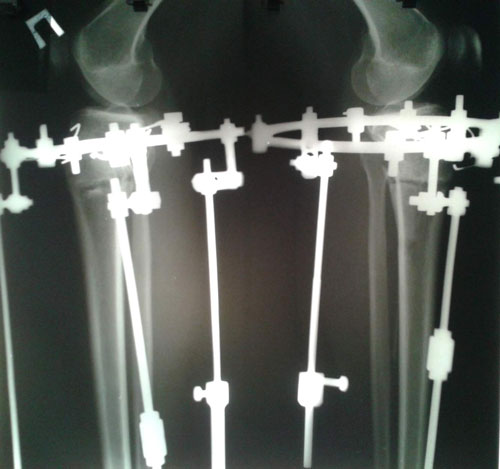

У пациентки плоскостопие 2-ой степени.

26 лет.

Дата операции 08.10.2015г.